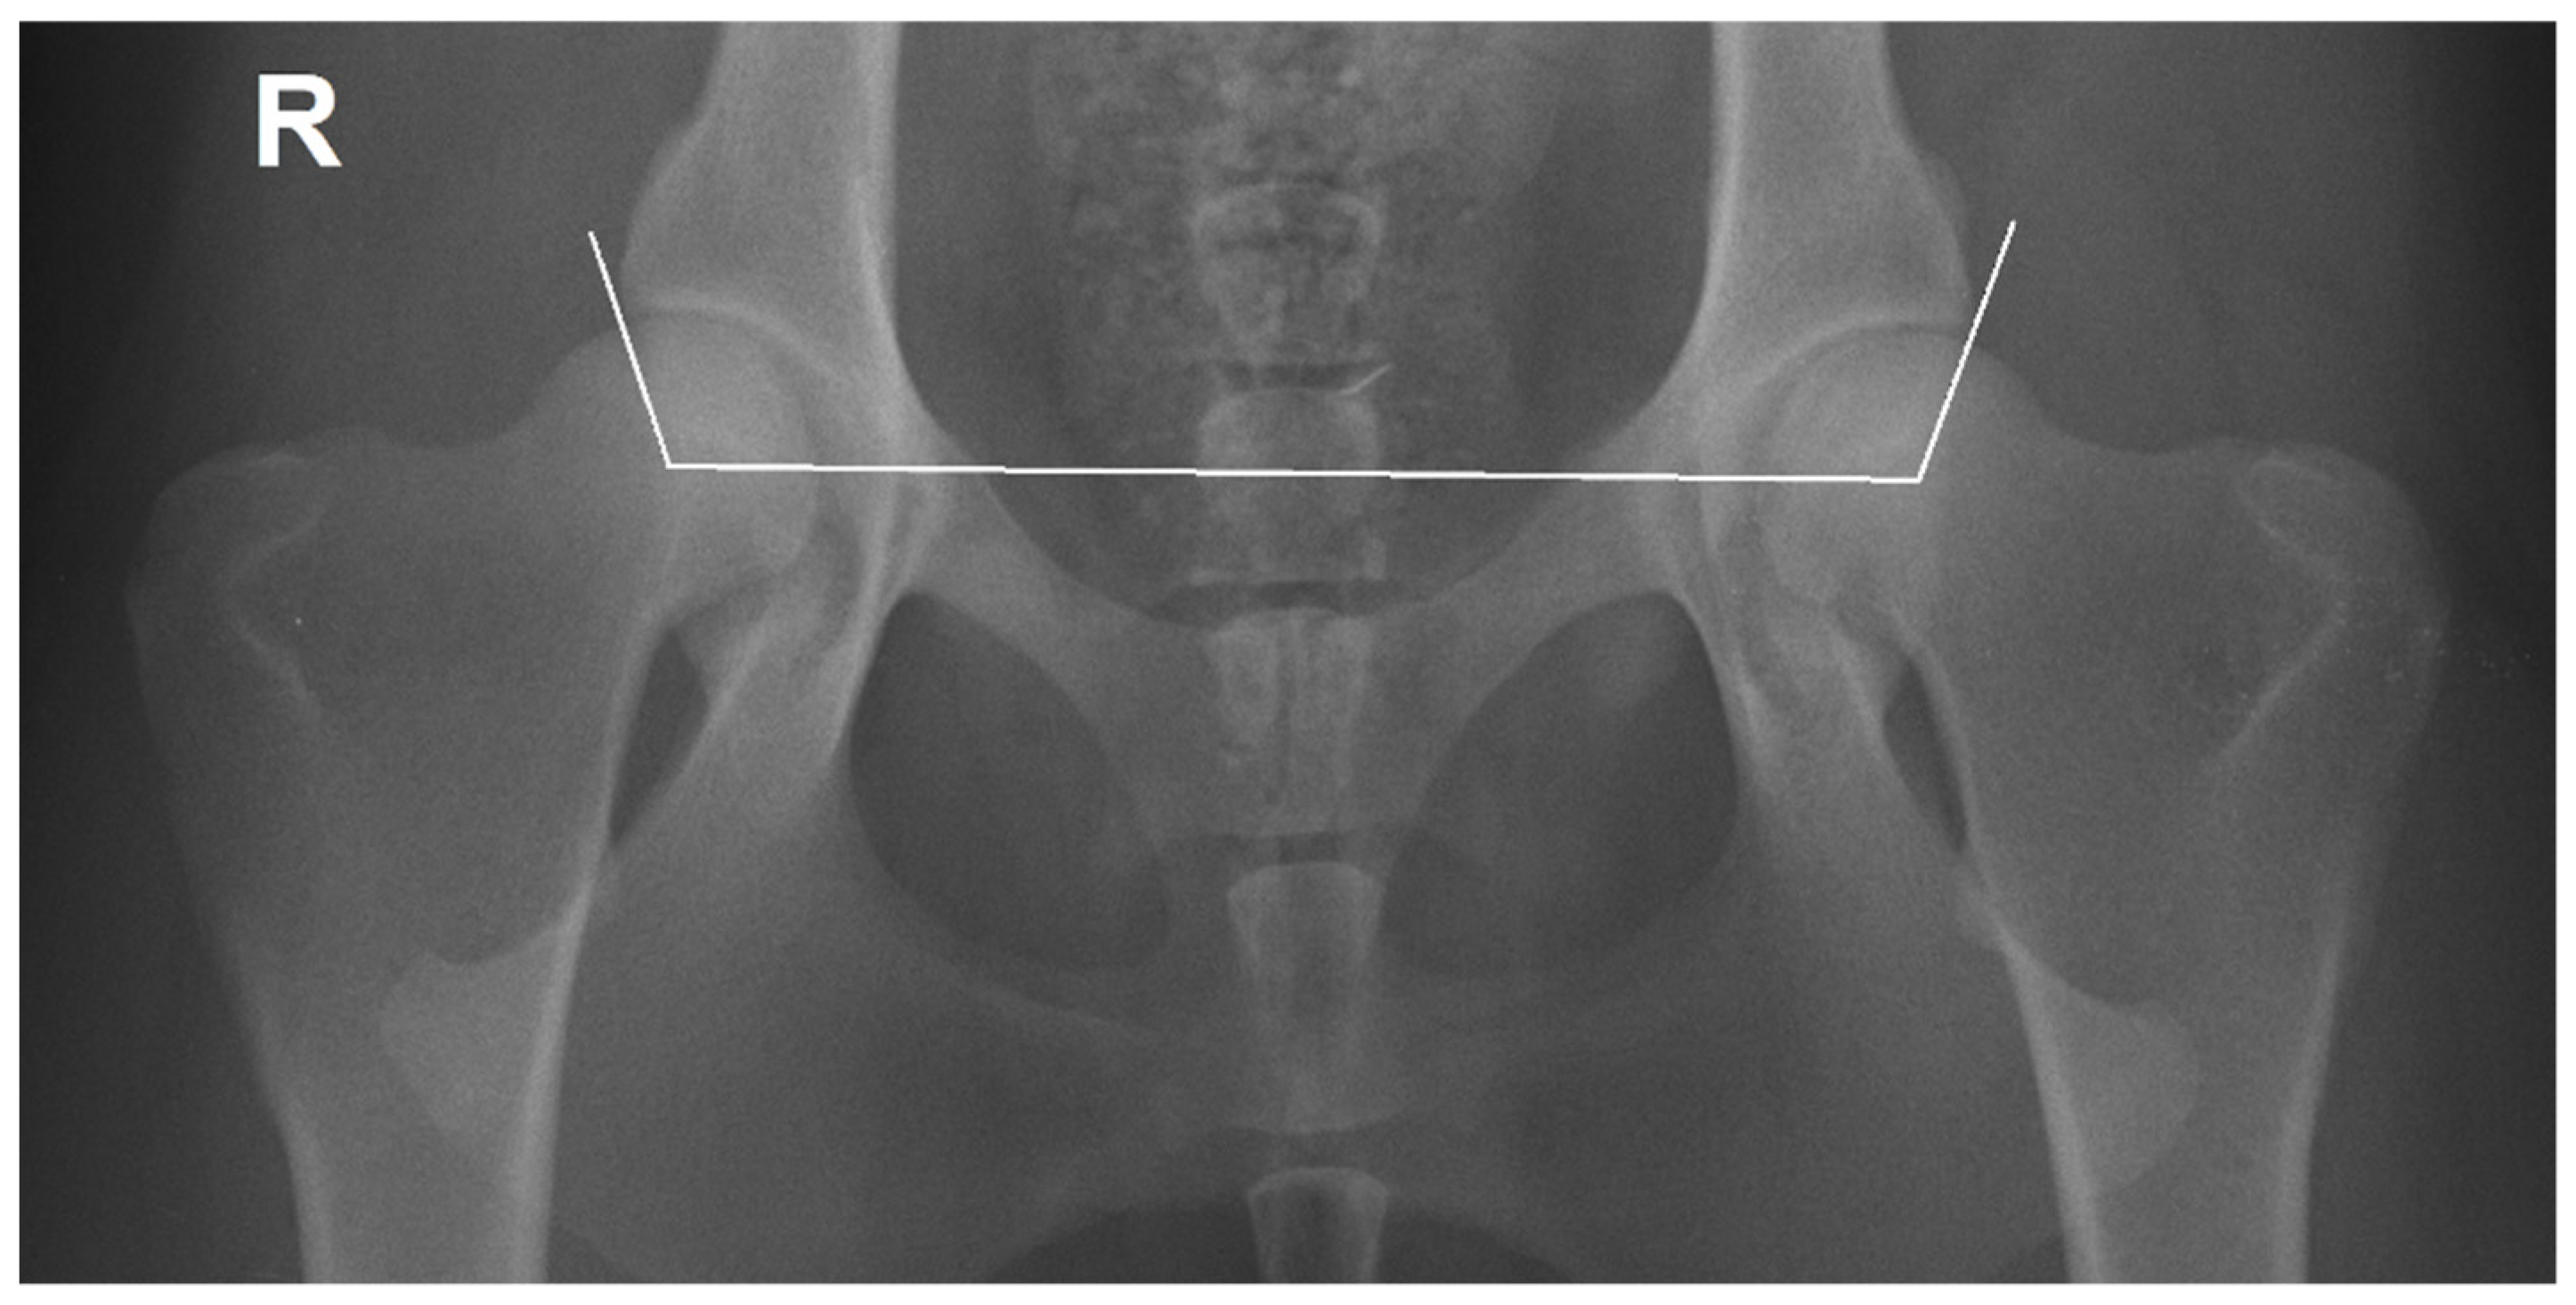

2.1. Radiographic Measurements